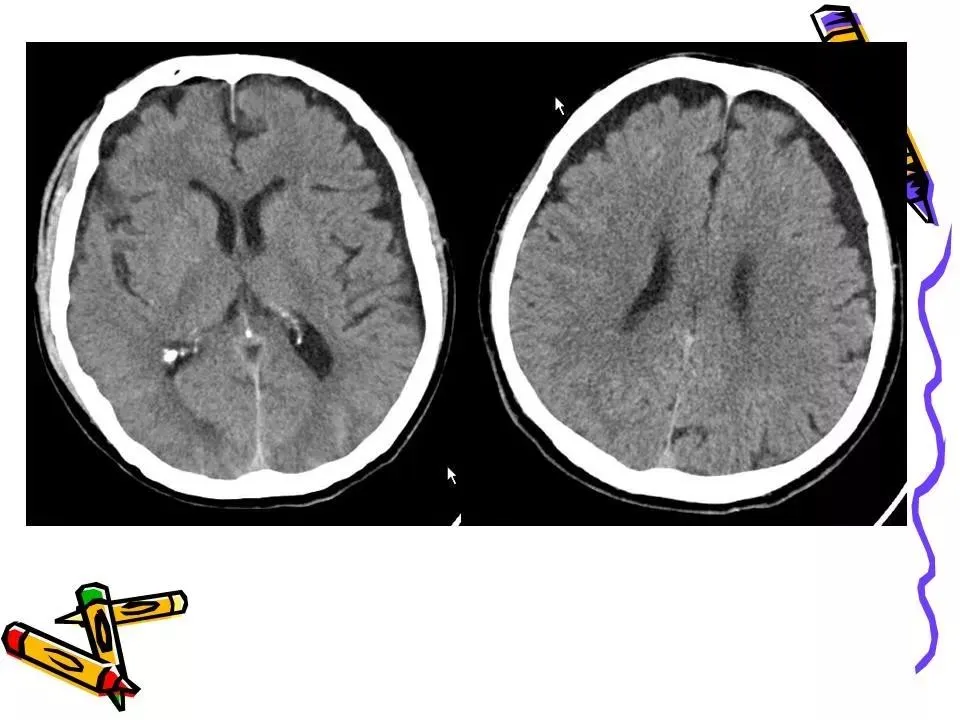

>常见颅脑外伤CT诊断(PPT)

常见颅脑外伤CT诊断(PPT)